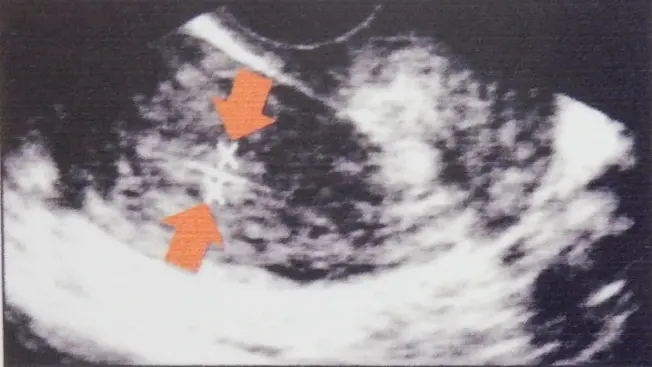

子宮内膜に対する鍼灸治療の効果

「明生鍼灸院」と「おち夢クリニック名古屋」の共同研究より、高度生殖医療と鍼灸治療を併用した57症例の結果:

鍼治療前

3層構造5㎜

鍼治療6か月後

3層構造8㎜

内膜形状の改善群は54.4%、そのうち妊娠率は45.1%でした。